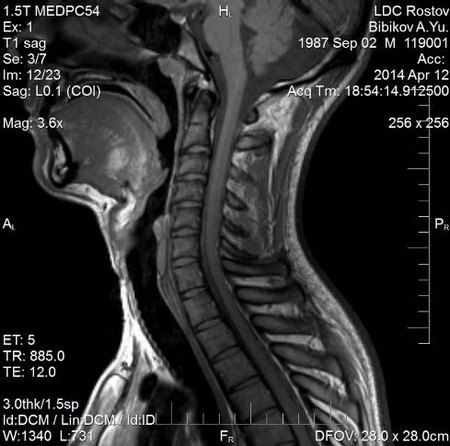

Прежде чем отвечать на вопрос, видно ли горло на МРТ шеи и что можно увидеть при его сканировании, следует пояснить, что входит в понятие «горла». В область сканирования входят ротоглотка, гортаноглотка, гортань, соответствующие сосуды, часто исследование включает и сканирование щитовидной железы.

МРТ диагностика на сегодняшний день является самым безопасным, неинвазивным и наиболее информативным методом обследования органов горла.

Если Вы приняли решение провести МРТ горла ребенку или себе, первым делом при выборе центра стоит поинтересоваться, делают ли МРТ шеи на низкопольном или на высокопольном аппарате. Если цель томографии- поиск онкопроцесса или дифференциация объемного образования, то следует использовать только закрытый аппарат, если цель обследования- рутинная (нежизнеугрожающая) патология, то достаточно мощности открытого сканера. Также открытые аппараты предпочтительнее для сканирования детей, так как профиль таких устройств позволяют родителю находиться рядом и быть в поле зрения ребенка.

Подготовки к нативному обследованию не требуется, при введении контраста- не рекомендуется есть за три часа до процедуры. Во время сканирования на область шеи помещают радиочастотную катушку в виде полукольца. Время сканирования занимает около 30-40 минут, при этом пациент должен соблюдать полную неподвижность, глотать также запрещается, ввиду этого детям чаще всего проводят МРТ под действием наркозных средств.